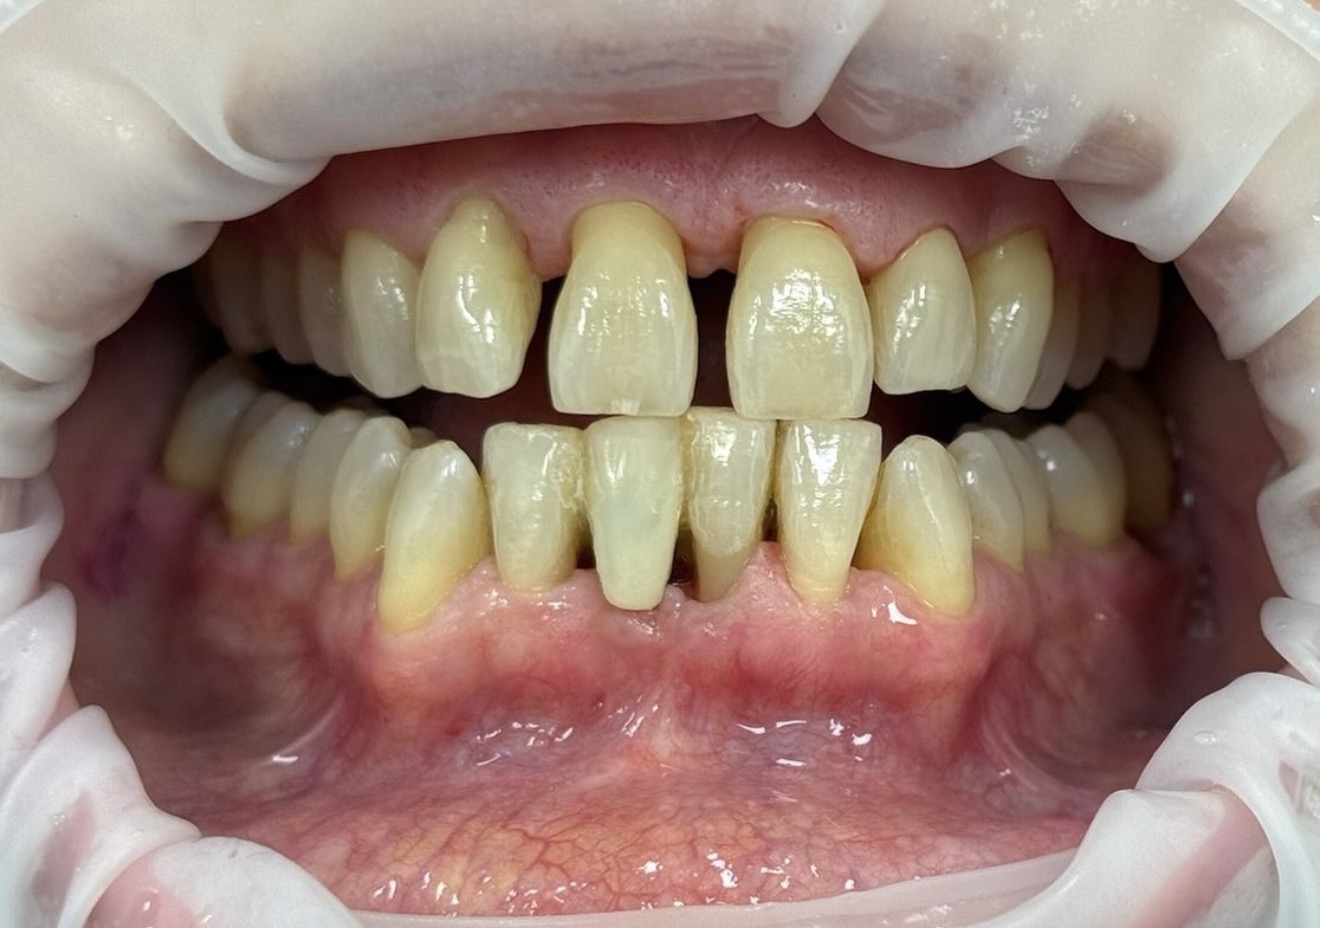

Perché la verità è che molto spesso la Parodontite viene trascurata, non solo dal paziente, ma anche da noi professionisti. Si decide infatti di intervenire quando ormai ci sono già i segni evidenti che la malattia sia in uno stadio avanzato. Magari quando il paziente ha bisogno già di qualche estrazione dentaria.

La verità è che questa malattia è molto diffusa, soprattutto nella popolazione adulta (si stima che ne soffra circa il 60% delle persone sopra i 30 anni). In molti casi, però, i sintomi della parodontite sono lievi (gengiviti, ipersensibilità) e solo dopo un attento esame clinico o dopo una radiografia possono essere valutati come indici di parodontite. Per questo motivo sia il paziente che il dentista generico che vede abitualmente il paziente potrebbe trascurare alcuni segni importanti.

Dopo la prima visita, il paziente in cui sono riconosciuti i sintomi della parodontite viene indirizzato verso percorsi più specifici. Alla radiografia panoramica che ci fornisce un quadro generale della situazione dentaria, viene affiancata la sistematica radiografica. Questo esame consiste in una serie di radiografie endorali di piccole dimensioni, in cui è possibile osservare dente per dente: livello dell’osso, presenza di tartaro calcificato, forcazioni radicolari compromesse, etc. Il limite di questo esame è che non fornisce un dato tridimensionale, per questo motivo va integrato con la cartella parodontale. Questa consiste nella misurazione dente per dente della profondità della tasca gengivale intorno agli elementi dentari, su 6 punti. Durante questo processo vengono rilevati anche la presenza di placca, sanguinamento e mobilità. Questo fornisce un quadro iniziale completo della situazione del paziente affetto da parodontite.